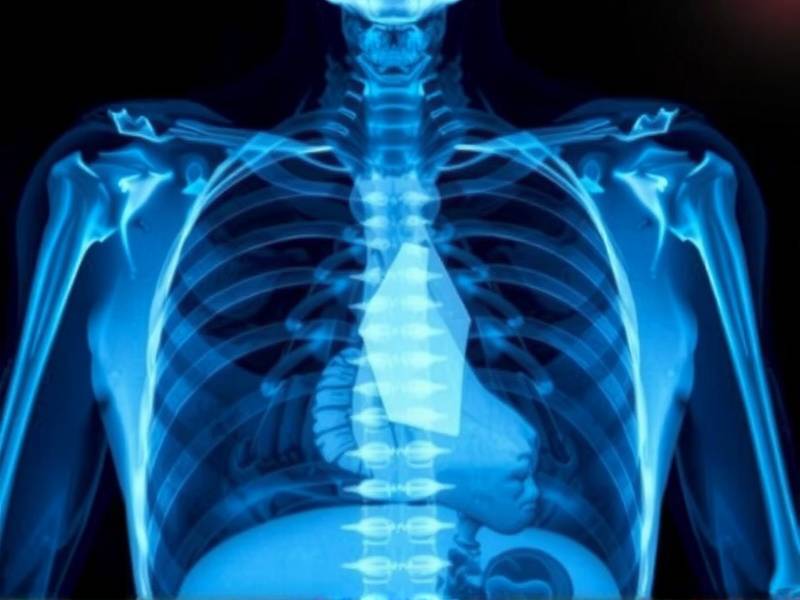

Visualization of Damage: A Strong Motivator

The visual impact of a chest X-ray can be powerful. Seeing the tangible damage smoking has caused to one's own lungs can serve as a stark reminder of the risks involved. This visualization often serves as a strong motivator for smokers to quit, as it makes the consequences of continued smoking all too real.